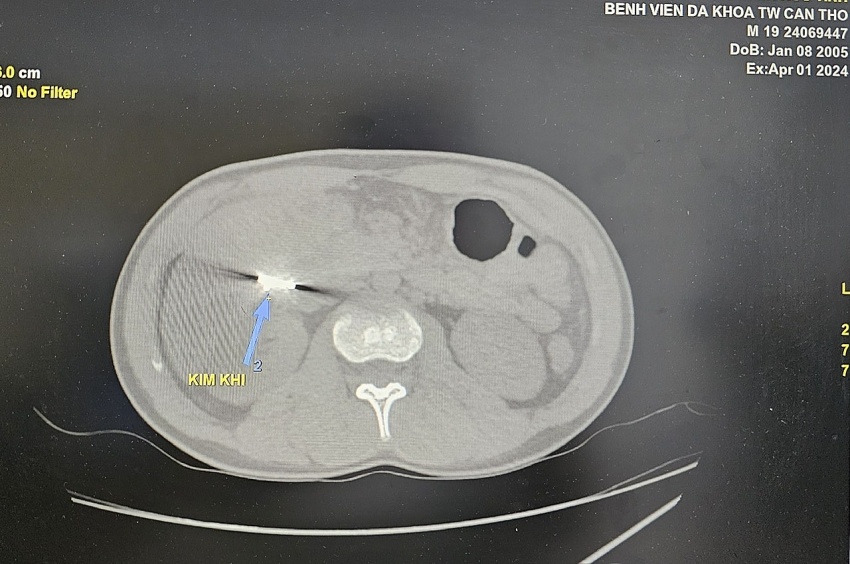

Ngay khi nhập viện, các bác sĩ Bệnh viện Đa khoa Trung ương Cần Thơ tiến hành thăm khám khám và thực hiện các xét nghiệm. Kết quả chụp cắt lớp vi tính bụng có cản quang ghi nhận dị vật cản quang kim loại dưới gan phải kích thước 2x1cm, áp xe vùng hạ sườn phải kích thước 5x3cm.

Hình ảnh dị vật từ kết quả soi chiếu.